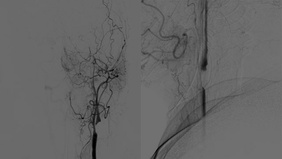

From Invisible to Curable Endovascular Cure of a Heubner’s Micro-AVM in a Child

By Nguyen Ngoc Minh LE

Published on December 11, 2025